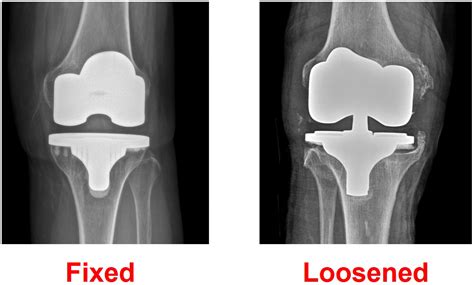

• Implant Placement: Securing the metal and plastic components that act as the new joint.

Many patients worry about pain management, the appearance of the surgical site, and the longevity of the implant. By watching a professional Total Knee Replacement video, you can witness the precision involved in modern robotics-assisted surgery, which often leads to smaller incisions and more accurate alignment. This knowledge helps address common misconceptions, such as the idea that the entire knee is “replaced.” In reality, the procedure is more of a resurfacing of the joint, where only the diseased bone and cartilage are removed and replaced with high-durability prosthetic materials.

Modern advancements have revolutionized the orthopedic field. If you search for a recent Total Knee Replacement video, you will likely encounter techniques involving computer navigation or robotic arms. These tools allow surgeons to customize the fit of the implant to your specific anatomy, potentially increasing the lifespan of the prosthetic and improving overall joint function. Watching these advanced techniques can provide extra peace of mind, demonstrating that modern surgery is highly personalized rather than a “one size fits all” operation.